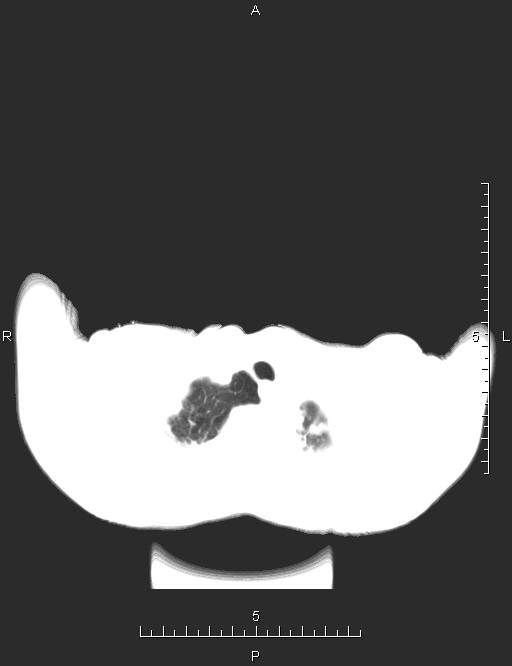

CT50170:胸部CT

本帖最后由 cefcmj 于 2015-4-1 17:31 编辑 女,75岁,反复咳嗽、咳痰、喘憋4年。

考虑“左肺中心性肺癌伴肺内多发转移,胸膜转移,心包转移。

多考虑左肺中心型肺癌伴肺内多发转移 左侧胸膜转移 心包转移。

继发性肺结核待除外。

左肺中心型肺癌伴肺内转移,左胸膜与心包转移